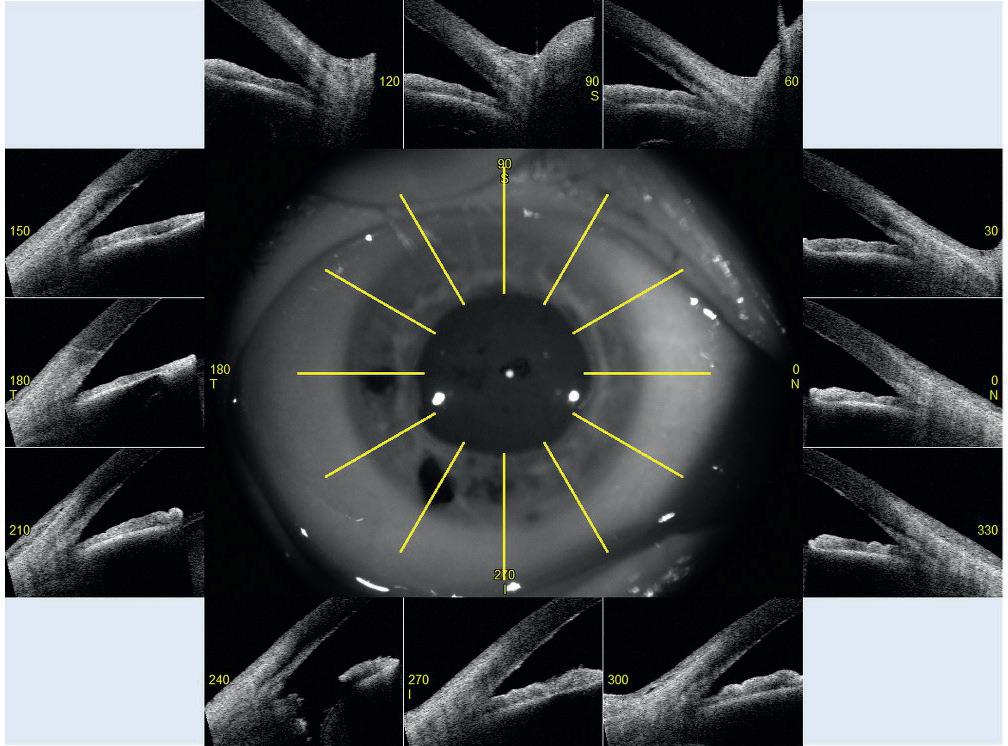

CASIA2 images inform us about corneal transparency and good adaptation of the endothelial graft, but also allows us to visualise the integrity of the lens after inferior iridectomy and gives us a 360° visualisation of the iridocorneal angle (figure 2).

In this case, a narrow angle with no presence of previous synechiae in all four quadrants is observed (figure 3). Given this situation, cataract surgery will be proposed with pupillary sphincter reconstruction using iris cerclage, with no associated glaucoma surgery as part of the procedure at this time.

Figure 2

Figure 3